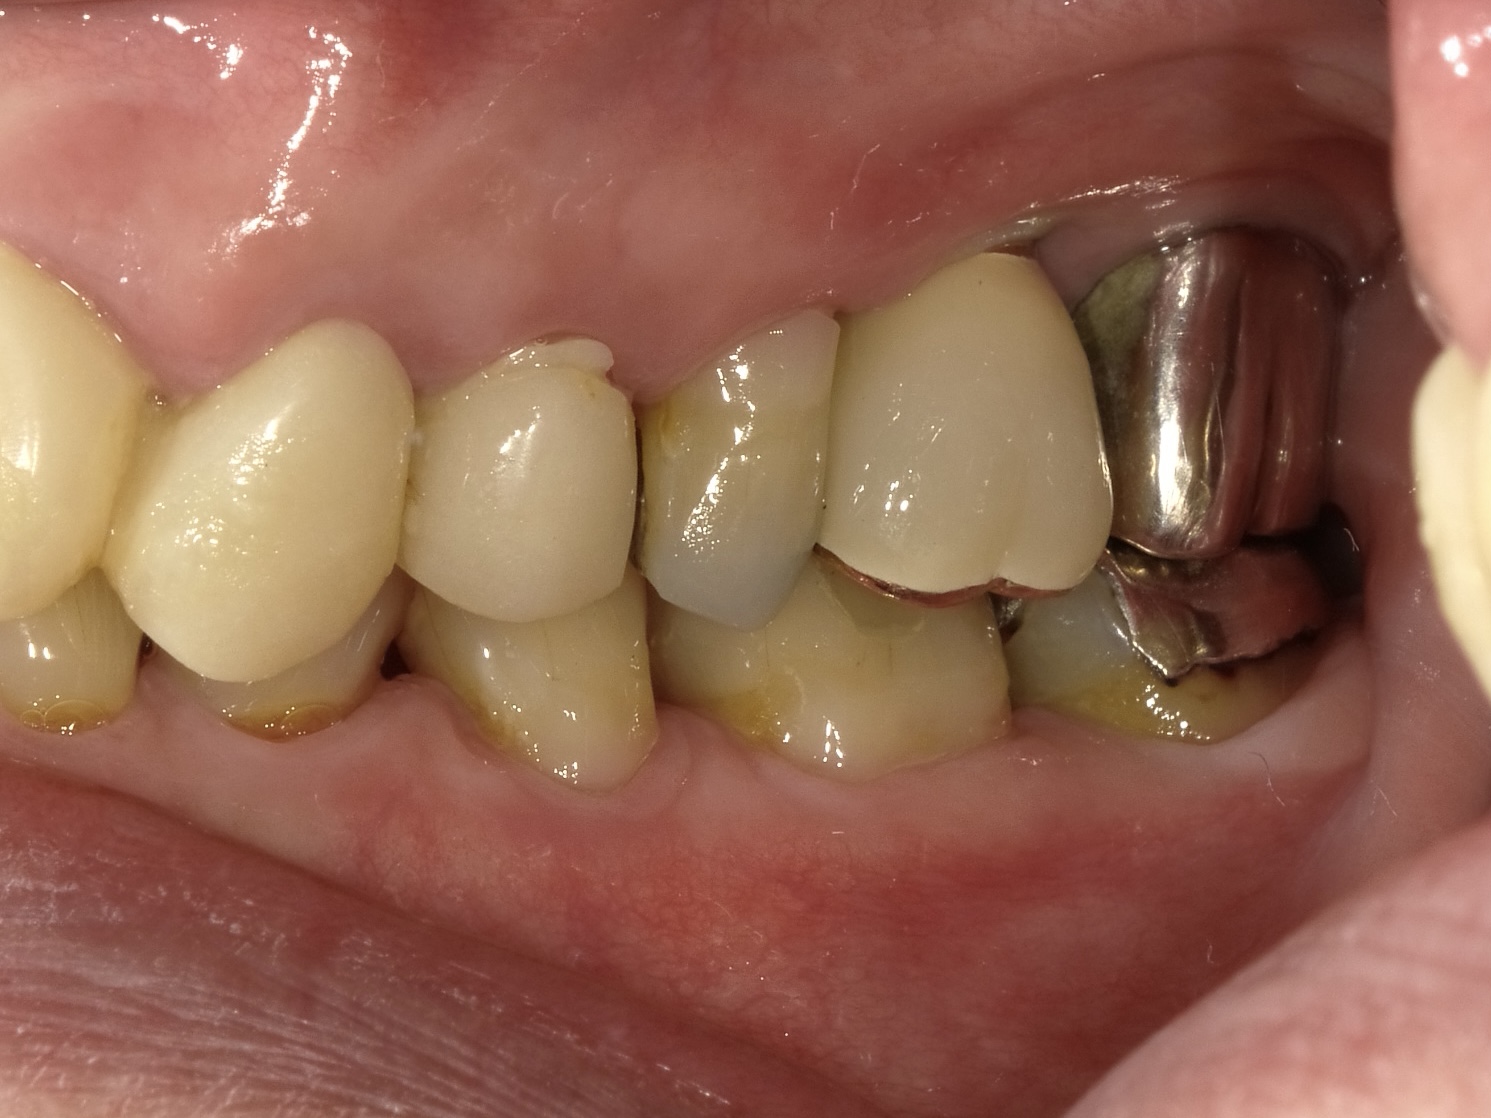

左上6番 抜歯即時インプラント埋入

BEFORE

AFTER

| 金額 | ¥450,000(税抜) |

| 期間 | 約3ヶ月 |

| リスク | オペから6週までは過大な力がかかると骨の2次安定が得られないことがあるため、注意を要する。 |